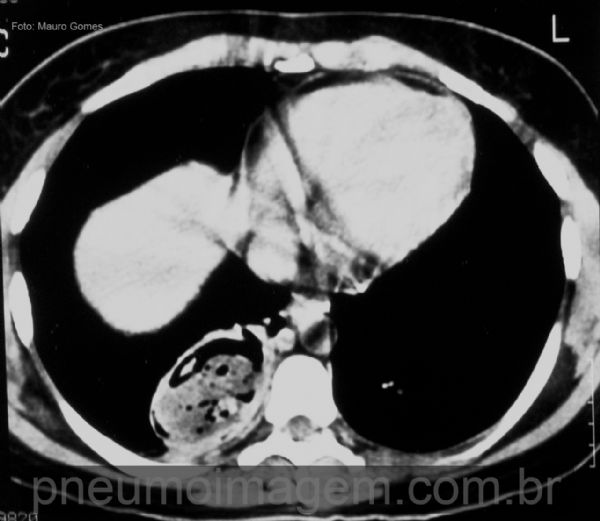

Bronquiectasias podem estar associadas à lesão, como se observa neste corte com janela para mediastino. O diagnóstico do sequestro é realizado através da demonstração da origem anômala da vascularização por meio de angiotomografia ou angiografia convencional.

Bronchiectasis may be associated with sequestration. The diagnosis of sequestration is performed by demonstrating the anomalous origin of the vasculature by angiotomography or conventional angiography.